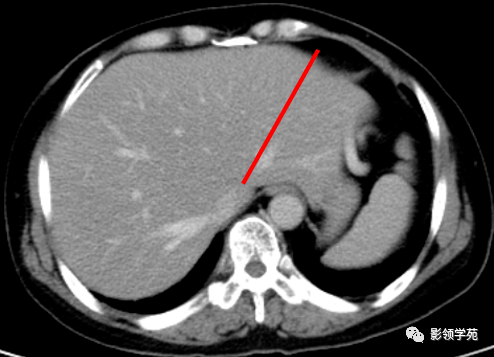

肝couinaud分段的ct影像学

肝脏分叶分段的影像学解剖

上腹部ct断层肝脏解剖及肝段分布腹部淋巴结分布